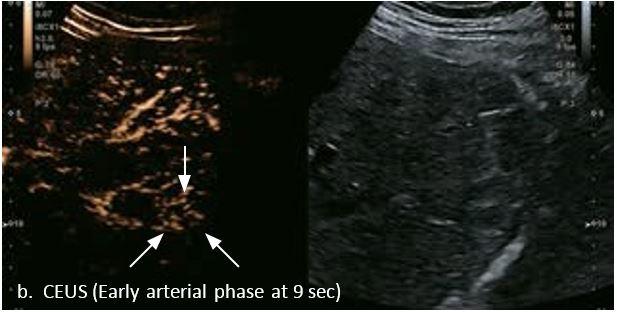

LI-RADS 4 множинні ГЦК

Це випадок 60-річної жінки з декомпенсованим цирозом печінки з асцитом. На сірошкальному зображенні можна виявити два вогнищевих ураження, розміром 21 мм і 10 мм відповідно, розташовані в сегменті 5. Оскільки дослідження методом зсувної хвилі на апараті Canon виконується штовхаючим імпульсом, пацієнтам з асцитом не можна проводити дослідження за допомогою зсувної хвилі, для визначення стадії фіброзу. На ранній артеріальній стадії гомогенне гіперехогенне підсилення спостерігається в обох ураженнях. Ураження є ізоехогенними в портальній венозній та пізній фазах, вимивання не спостерігається через 6 хвилин після ін'єкції, тому ці ураження були класифіковані як LI-RADS 4, ймовірна ГЦК. Важливо знати, що LI-RADS 5 - це ГЦК зі 100% вірогідністю, і вона не потребує біопсії. Значна кількість LI-RADS M (ймовірно або точно злоякісні, але не специфічні для ГЦК) і LI-RADS 4 (ймовірна ГЦК) насправді являються ГЦК.

Малюнок 11